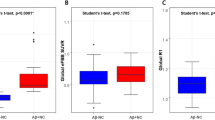

The differences in the cortical amyloid depositions and FDG uptake of the patient groups (Groups B to D) relative to the normal control (Group A) are pictorialized in Fig. 2. There was a slightly higher cortical uptake of florbetapir in the visual association (BA19) and parietal cortices, anterior prefrontal /anterior cingulate cortices (BA10), the precuneus (BA7), and temporal cortices (BA21) in Group B than in Group A (Fig. 2a). However, compared with Group A, the cortical amyloid deposition in Group C was significantly higher in the occipital cortex (BA19, BA17) as well as being significantly higher in the precuneus (BA7), anterior cingulate (BA32), posterior cingulate (BA23, BA31), temporoparietal (BA22, BA39), and frontal cortices (BA11) (Fig. 2b). A similar pattern was also detected when Group D was compared with Group A, but with slightly more extensive regions and with higher amyloid depositions, including in the lateral and medial occipital cortices (BA 17 and 18) (Fig. 2c). Details of the locations of the regions showing significantly increased florbetapir uptake in the Group A-to-D subjects are given in Table 2. The regions located in occipital lobe (BA17, BA18, and BA19) partly show higher amyloid deposition in every group comparison. The box-and-whisker plot graph of mean and SD of each group’s mean cortical SUVR is also demonstrated (Fig. 2d).

Comparison of the regional amyloid deposition across participants in Groups A–D. There was no significant difference in occipital amyloid deposition between Groups A and B (a). However, significantly higher cortical amyloid deposition at the occipital cortex was noted in both Groups C (b) and D (c), relative to Group A, in addition to other regions, namely, the precuneus, anterior cingulate, posterior cingulate, temporoparietal, and frontal cortices (P < 0.001, uncorrected). The box-and-whisker plot graph shows mean and SD of each group’s mean cortical SUVR (2D)

When we first estimated the amyloid deposit correlation using threshold P < 0.001, uncorrected almost the whole brain area was negatively correlated, but the occipital cortices had the strongest correlation (Fig. 4). Then, after using strict criteria P < 0.05, FWE, only the occipital cortices survived (Fig. 5; Table 3). Significant correlations between FDG uptake and TMSE were demonstrated in the bilateral parietotemporal and frontal as sociation, posterior cingulate, and precuneus cortices (Fig. 6).

The voxel-based analysis from florbetapir PET data in all 58 participants resulted in a strong negative correlation between the occipital cortical uptake and the TMSE score (P < 0.05, FWE) (a). Scatter-plot graph shows the relationship between the occipital SUVR (x) and TMSE scores (y) in all subjects (b)